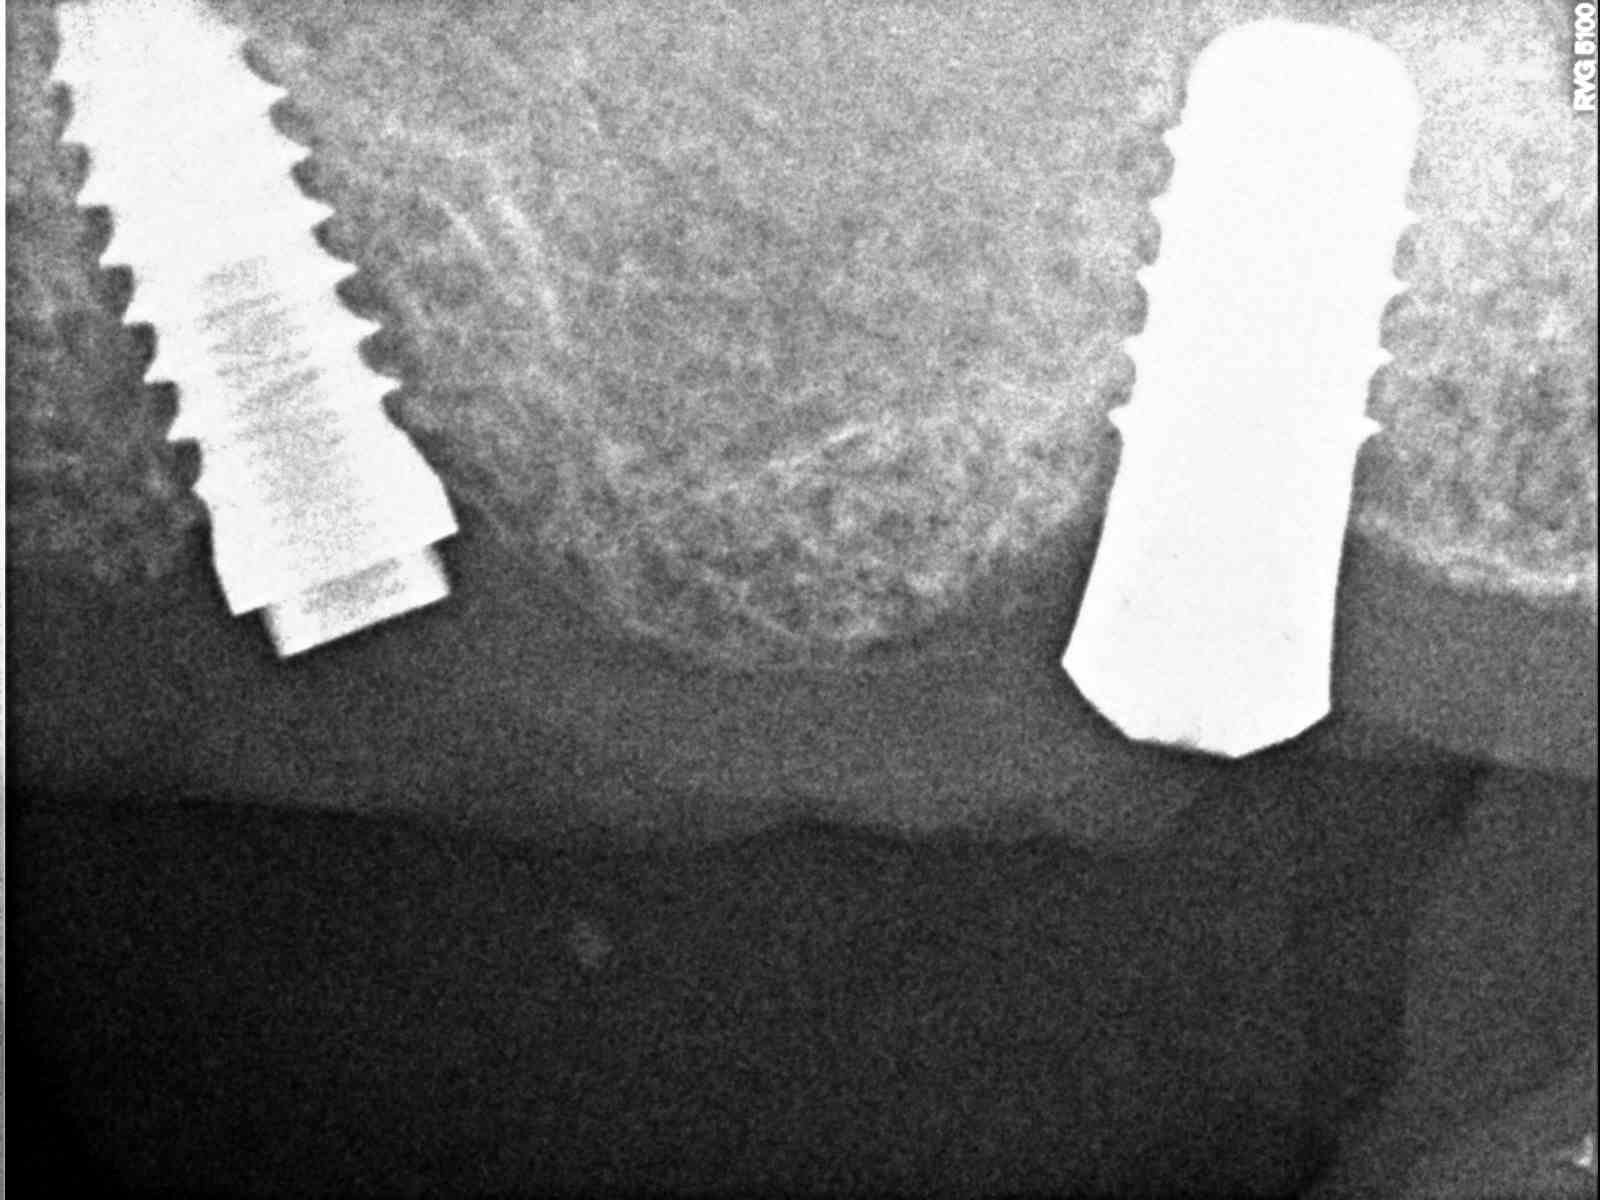

Que implante es 46?

Hace unos dias vino el paciente con la corona en la mano del implante 46. El tornillo se fracturo y conseguimos extraerlo. Necesitamos saber el sistema del implante para encargar [...]

Hola, nos ha entrado este caso para volver a rehabilitarlo y el paciente no tiene nada de información de los implantes. Necesitamos saber todo lo necesaria de todos los implantes [...]